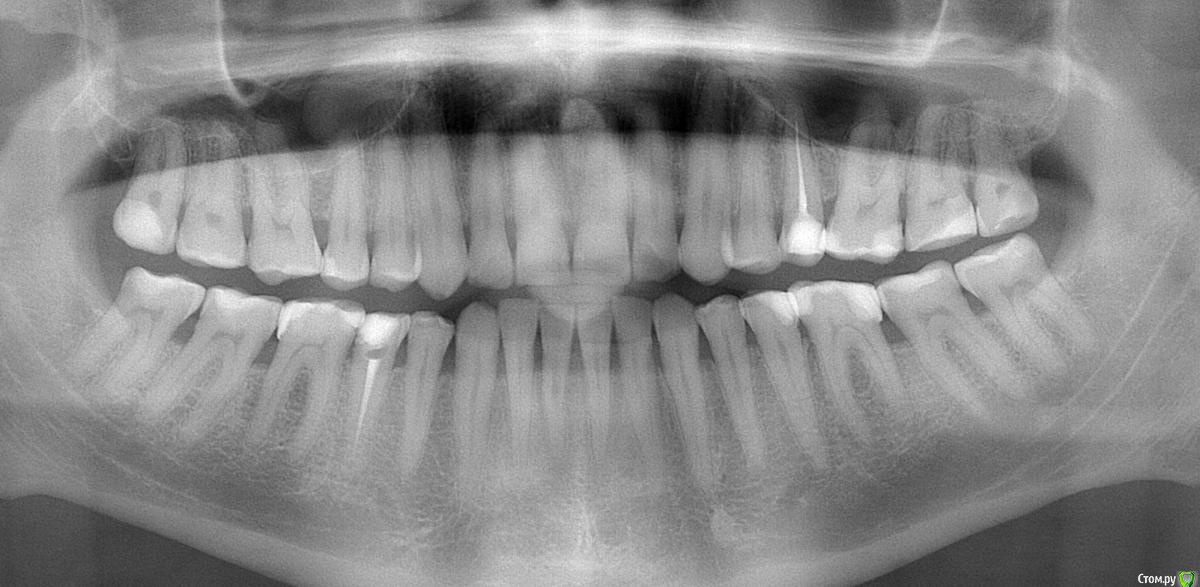

DmitrySH Опубликовано 11 апреля, 2017 Поделиться Опубликовано 11 апреля, 2017 Картинка из интернета нам мало интересна. Нужны объективные данные по вашей проблеме. сделайте панорамный снимок Ссылка на комментарий

Aleksandr_ Опубликовано 12 апреля, 2017 Автор Поделиться Опубликовано 12 апреля, 2017 (изменено) Сделал снимок.Нитка застревает, когда веду от десны.И чтобы освободить её, приходится вести в обратную сторону, к десне.Движением в сторону, перпендикулярно от зуба, освободить не удаётся. Изменено 12 апреля, 2017 пользователем Aleksandr_ Ссылка на комментарий

DmitrySH Опубликовано 12 апреля, 2017 Поделиться Опубликовано 12 апреля, 2017 Почти все пломбы имеют нависающие края, там и происходит ретенция налета и остатков пищи. Переделывайте, лучше всего керамические вкладки сделать вместо пломб. И к пародонтологу сходить на консультацию. Ссылка на комментарий

Aleksandr_ Опубликовано 14 апреля, 2017 Автор Поделиться Опубликовано 14 апреля, 2017 я так думаю, что какие-то места, где возможно, пломба не прилегает к зубу, может быть просто не видно из-за закруглённой формы зубов.Скажите, пожалуйста, технически сложно сделать такие пломбы, как на снимке, но чтобы материал плотно прилегал, и нитка за них не цеплялась? Ссылка на комментарий